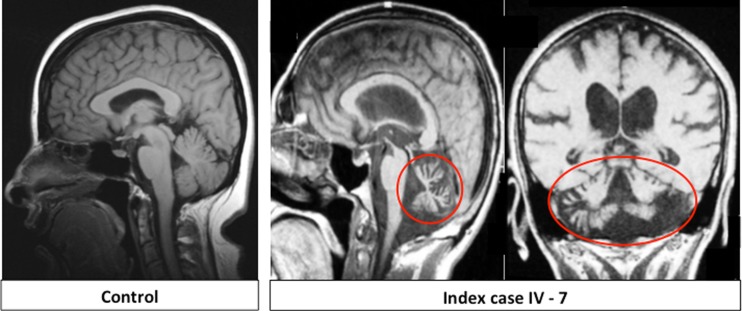

常染色体隐性小脑共济失调(ARCA)是一种主要影响小脑的临床和遗传异质性疾病。PNPLA6基因突变已被确定为遗传性痉挛性截瘫和与视网膜和内分泌表现相关的复杂形式的共济失调的原因,在这个领域,基因型-表型相关性正在迅速扩大。我们从居住在印度孟买的一个琐罗亚斯德教(帕西)大家族的一个近亲家庭中发现了两个堂兄弟,他们表现为纯粹的小脑性共济失调,没有绒毛膜视网膜营养不良或促性腺功能减退。我们使用临床特征、纯合子作图、全外显子组和Sanger测序相结合的方法来确定该家庭的遗传缺陷。家族表型为单纯小脑性共济失调。纯合子图谱显示,受影响个体之间在19p13染色体上有一个大的共享纯合子区域。在该区域内,索引病例的全外显子组测序在PNPLA6基因32外显子的c.3847G>A (p.V1283M)和c.3929A>T (p.D1310V)上发现了两个新的纯合错义变异。在这个大家庭中,两人都与疾病完全分离,只有两个受影响的表亲是纯合的。我们首次在一个常染色体隐性帕西家族中发现了与单纯小脑性共济失调相关的PNPLA6突变。该基因的先前突变与更复杂的表型相关,但这里的结果表明相关疾病谱系的扩展。

Autosomal-recessive cerebellar ataxias (ARCA) are clinically and genetically heterogeneous conditions primarily affecting the cerebellum. Mutations in the PNPLA6 gene have been identified as the cause of hereditary spastic paraplegia and complex forms of ataxia associated with retinal and endocrine manifestations in a field where the genotype-phenotype correlations are rapidly expanding. We identified two cousins from a consanguineous family belonging to a large Zoroastrian (Parsi) family residing in Mumbai, India, who presented with pure cerebellar ataxia without chorioretinal dystrophy or hypogonadotropic hypogonadism. We used a combined approach of clinical characterisation, homozygosity mapping, whole-exome and Sanger sequencing to identify the genetic defect in this family. The phenotype in the family was pure cerebellar ataxia. Homozygosity mapping revealed one large region of shared homozygosity at chromosome 19p13 between affected individuals. Within this region, whole-exome sequencing of the index case identified two novel homozygous missense variants in the PNPLA6 gene at c.3847G>A (p.V1283M) and c.3929A>T (p.D1310V) in exon 32. Both segregated perfectly with the disease in this large family, with only the two affected cousins being homozygous. We identified for the first time PNPLA6 mutations associated with pure cerebellar ataxia in a large autosomal-recessive Parsi kindred. Previous mutations in this gene have been associated with a more complex phenotype but the results here suggest an extension of the associated disease spectrum.